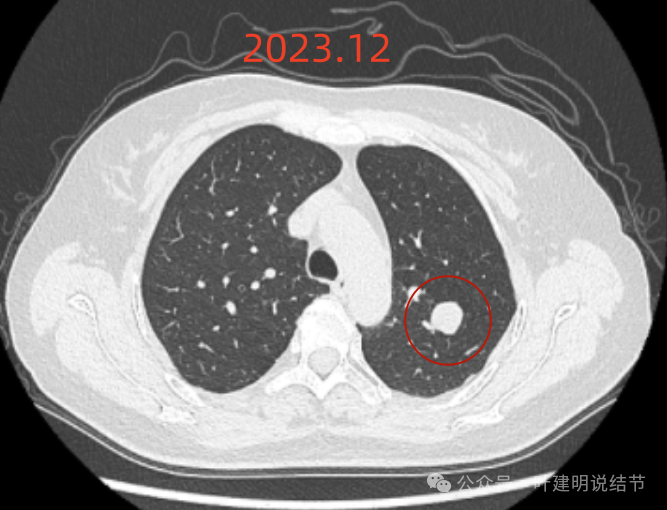

2023年12月,与血管已经贴着了。整体较最早时大了不少。

再来看2023年12月时连续层面的影像:

病灶出现,边缘区表面不是很光滑,似有少许磨玻璃成分以及边缘略显毛糙。

表面不是太光滑,中间的密度略显低。

血管贴得近,但没有牵拉或分支进入病灶,整体表面较为光滑。

与血管关系近,结节有膨胀感。

此层看与血管紧贴,没有间隙。局部有轻凹陷。

病灶明显感觉较为膨胀。

似见血管征,表面欠平滑,倾向浅分叶的样子。

边缘区密度不是太致密,有点像磨玻璃偏实的样子。

边缘区域混合密度的表现。

左上叶这个病灶看影像感觉边缘比较光滑,内部密度较为均匀,似乎是良性的。但我们如果将其2019年到2023年底的最大层面的影像放在一起对比,病灶是逐渐有增大的。2023年12月的肿块出现浅分叶、整体感觉鼓鼓的,原来病灶与旁边血管是有距离的,但最近这次的已经紧贴着了。但在纵隔窗看,病灶并无钙化或内部坏死密度,说明不太符合肉芽肿性炎或慢性炎性病灶。我觉得要十分倾向恶性肿瘤!低度恶性或交界性肿瘤可能性大。之前我碰到过随访10年的边缘光滑的实性病灶,从3厘米增大到8厘米多,术后是神经内分泌肿瘤的。我的想法还是要考虑切了,术前也可再复查下PET-CT,看看代谢是否活跃。但其实即使代谢轻度增高,也是放着不放心的。若是无代谢的,当然则与恶性不太符合(这种可能性是小的,无代谢不可能又增大)。这个位置穿刺可试试,但有点深,是否可行要与穿刺实施的科室医生沟通看看,若穿刺恶性仍得开刀,穿刺没见到癌细胞,但随访增大仍不放心。个人其实不是特别推荐穿刺。意见供参考!